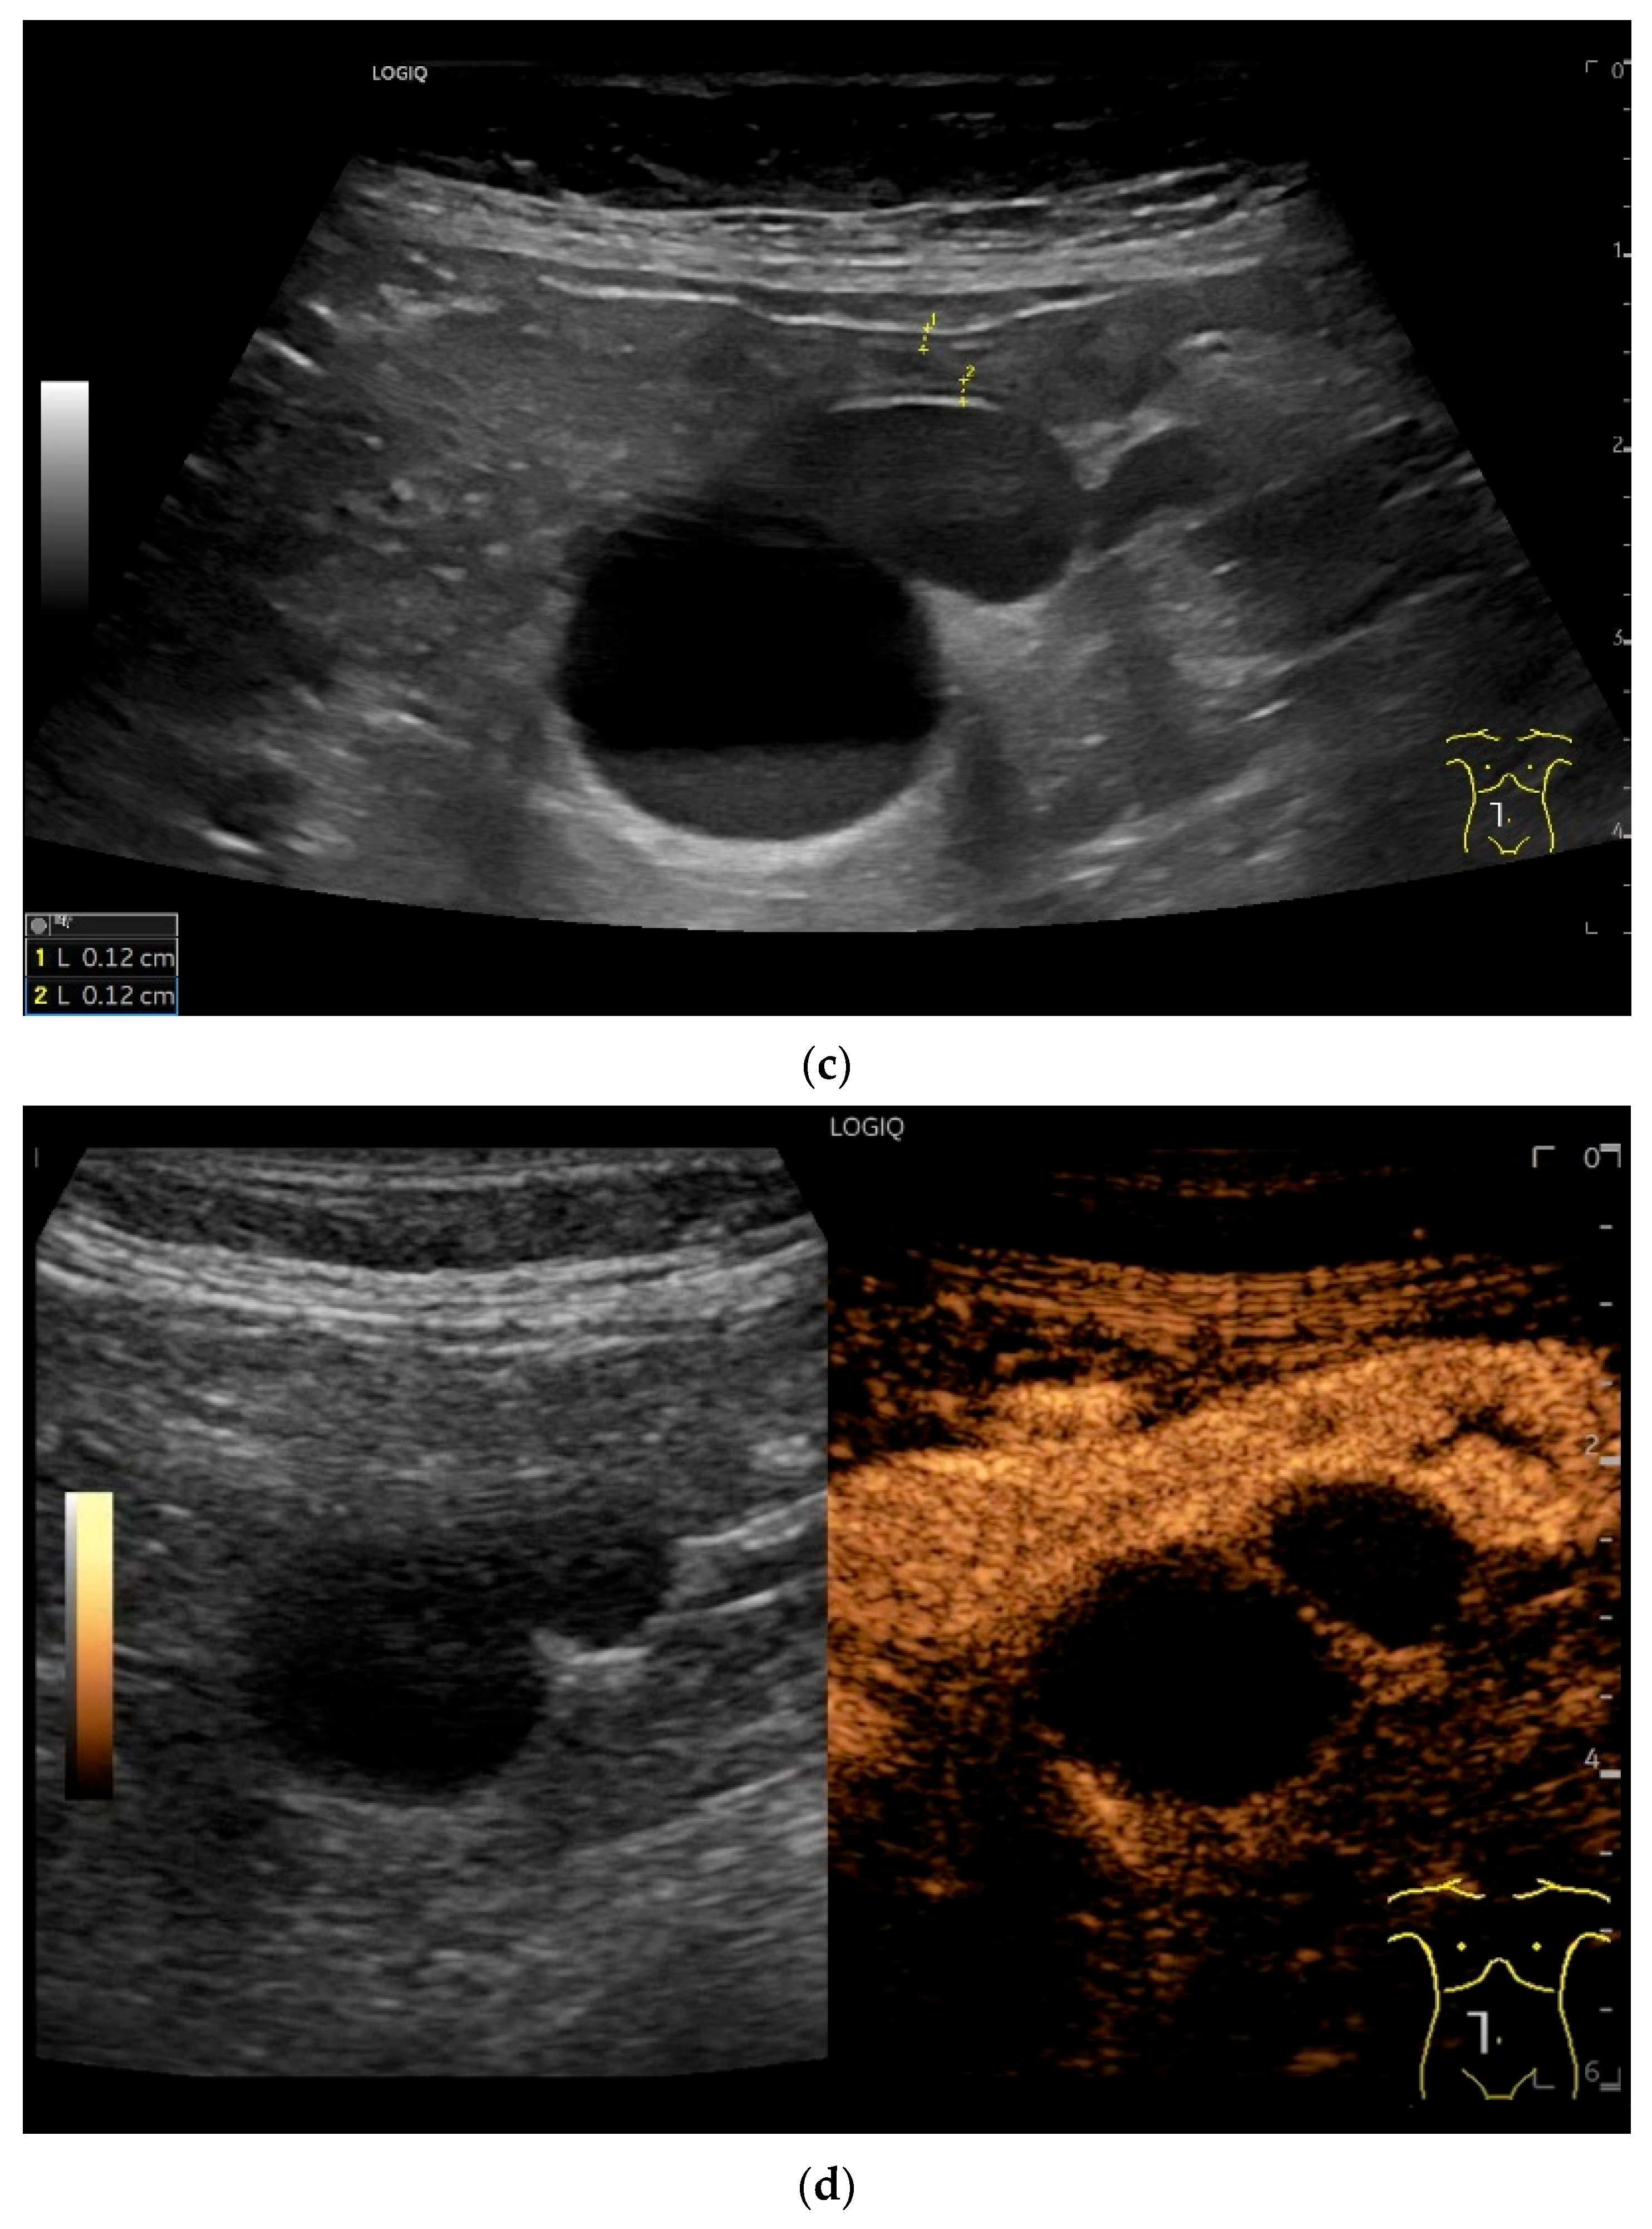

| Lymphangioma | Anechoic cystic lesions related to the small intestine wall. No vessels on CDI, Nonenhancement on CEUS. They move with the small intestine. |

| Intussusception | The small intestine proximal to the tumor is invaginated. More than five wall layers are seen in an onion-skin shape. |

- Rispo, A.; De Sire, R.; D’Armiento, M.; De Bonis, L.; Tropeano, F.P.; Ricciolino, S.; Nardone, G.; Luglio, G. Ultrasonographic diagnosis of ileo-ileal intussusception secondary to Vanek’s tumor. Eur. Rev. Med. Pharmacol. Sci. 2022, 26, 350–353. [Google Scholar] [CrossRef]